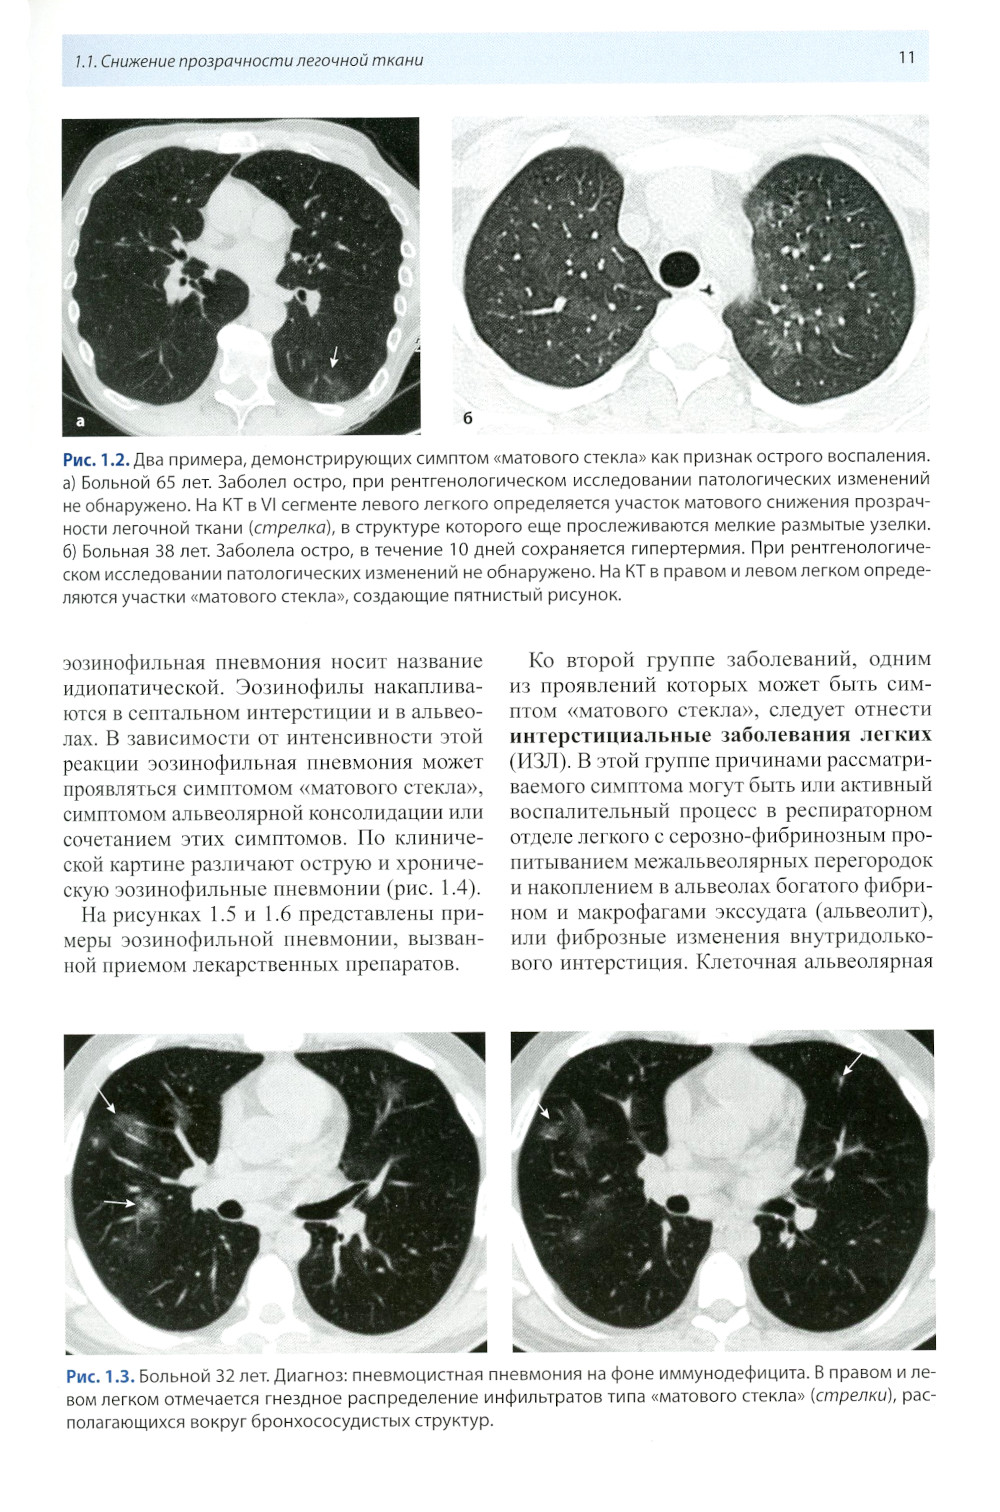

Книга составлена из двух разделов. В первом (глава 1) описаны основные симптомы патологии легких, выявляемые при КТ. Каждый из них представлен с позиции отображающих его морфологических изменений. В краткой форме описаны заболевания, проявляющиеся конкретным симптомом. Второй раздел книги состоит из трех глав, в которых отражены современные взгляды на наиболее часто встречающуюся патологию легких (пневмония, туберкулез, рак) и показаны возможности КТ в выявлении этих заболеваний. Издание предназначено для врачей лучевой диагностики, терапевтов, интернов и студентов старших курсов, интересующихся проблемами рентгенологии.| Издательство | МЕДпресс-информ |